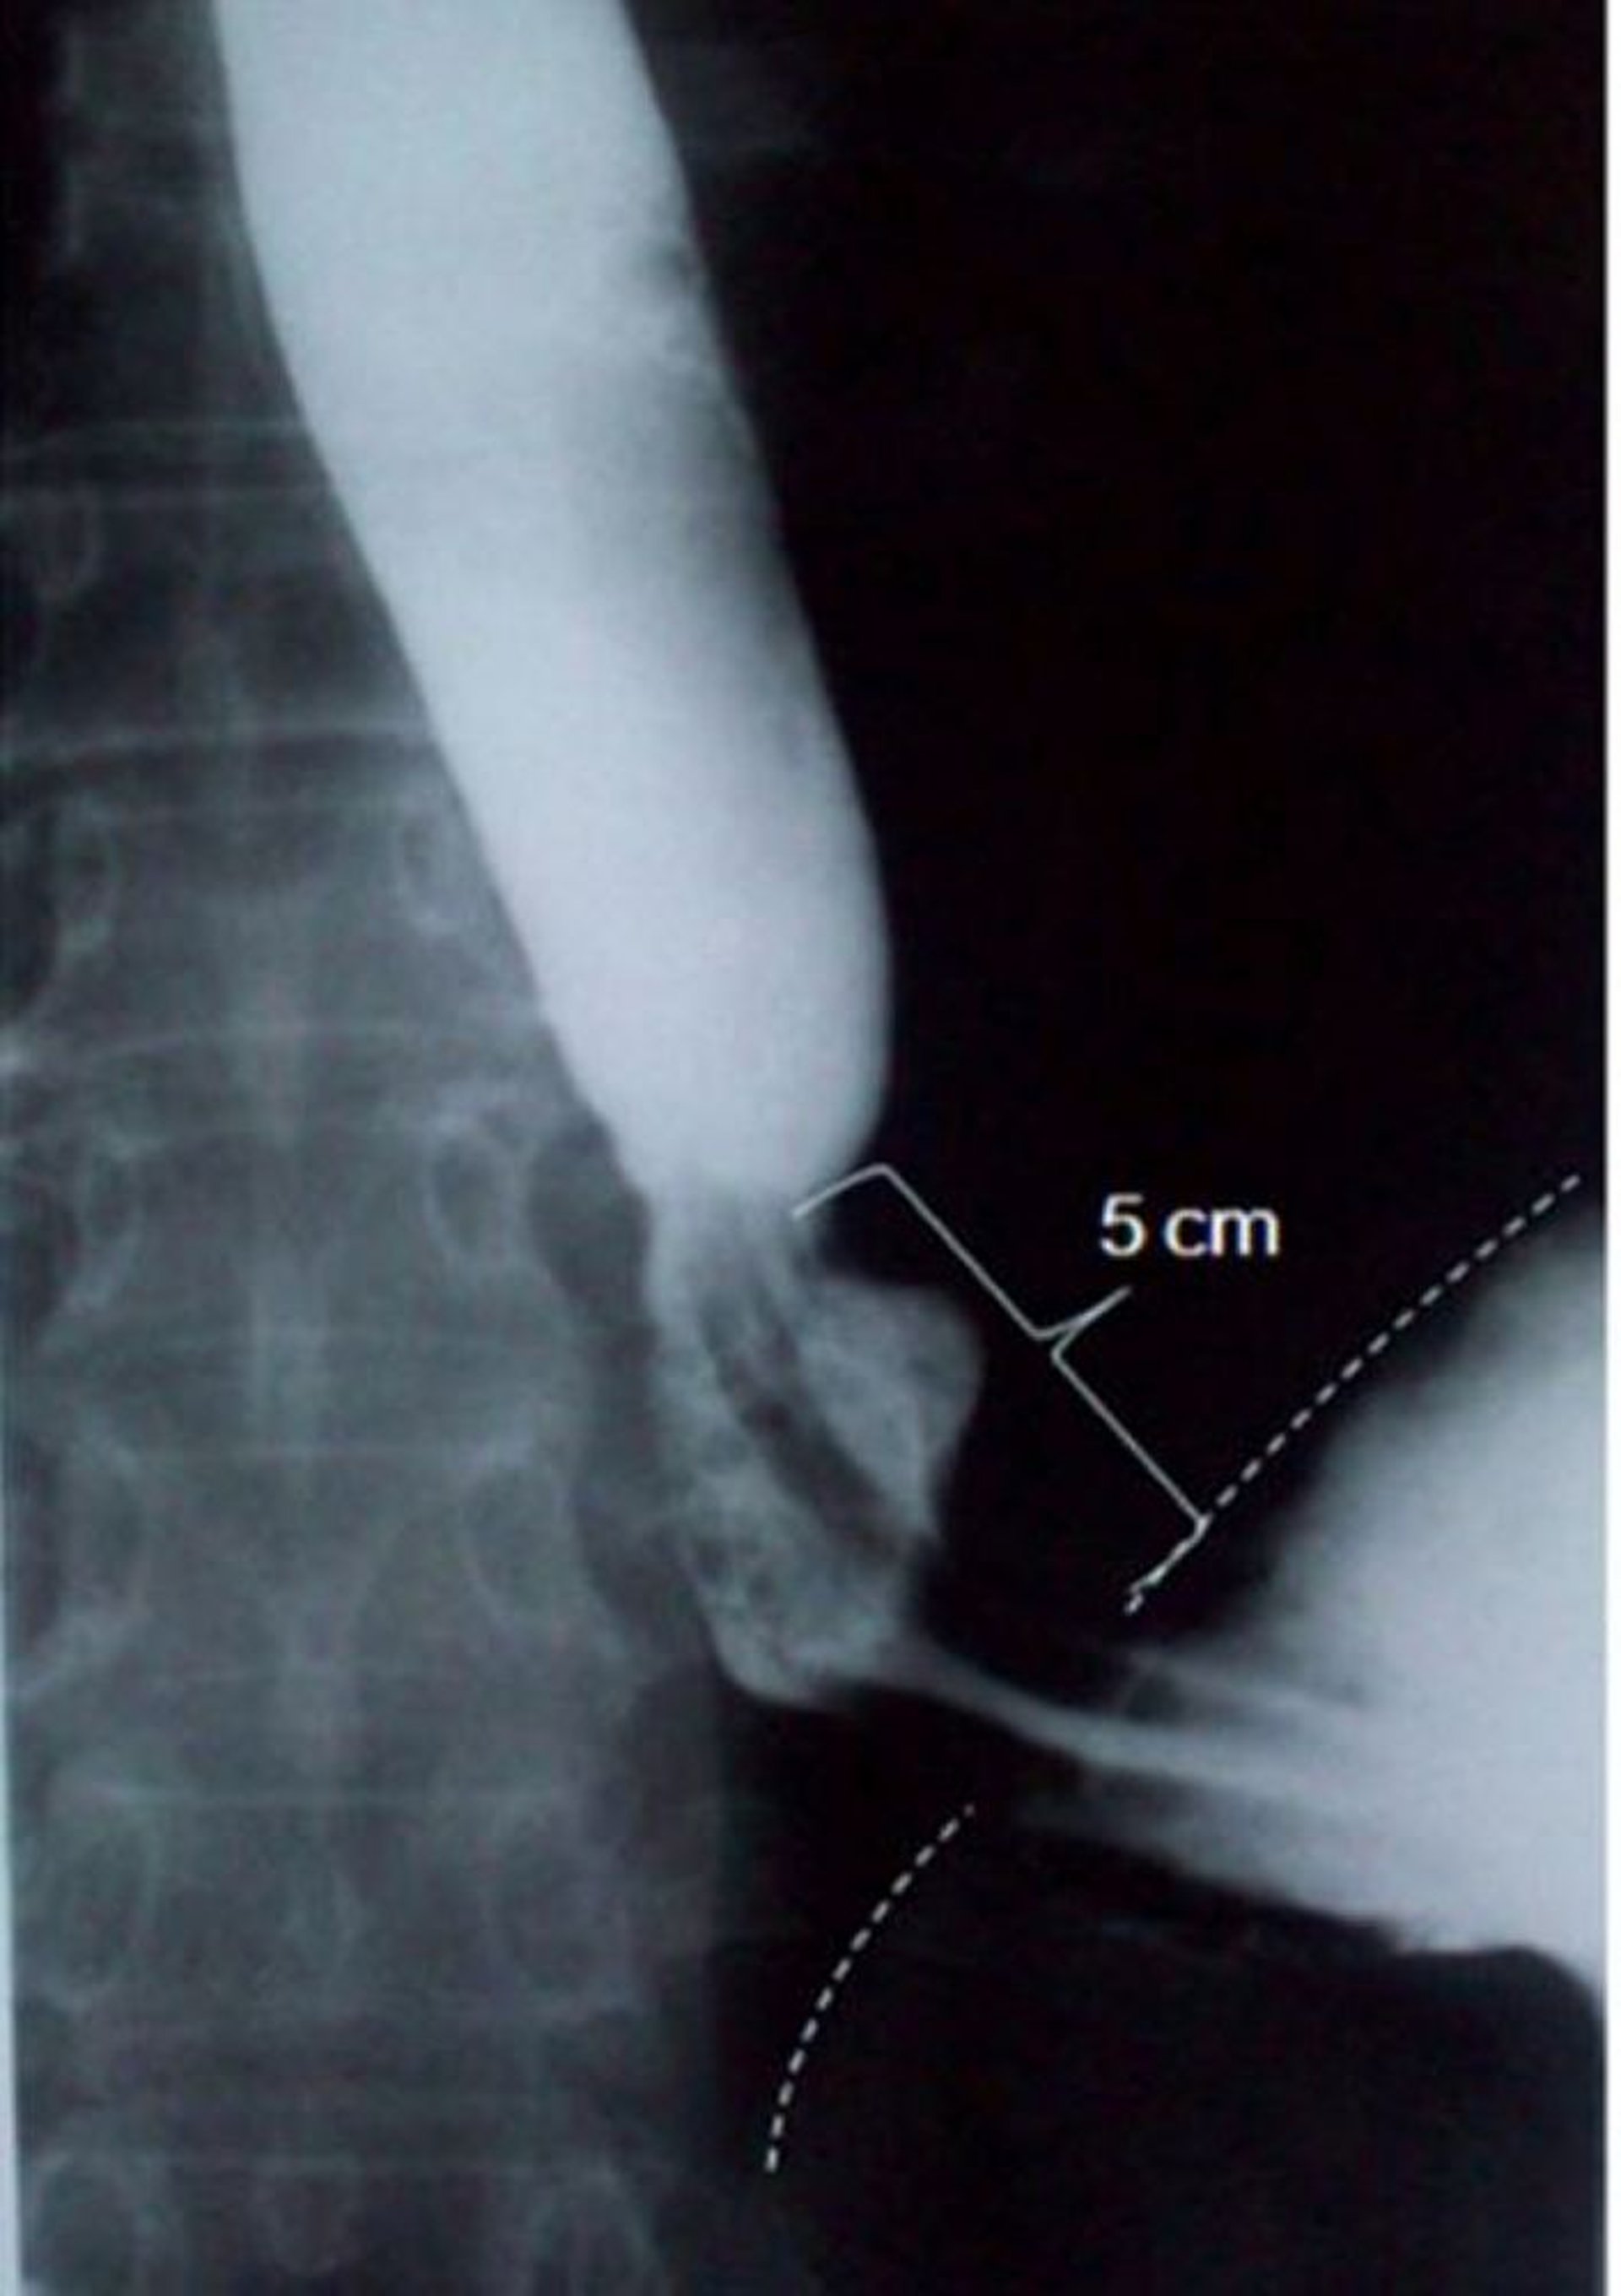

Trago de bario con hernia hiatal deslizante

Esta imagen muestra una hernia hiatal deslizante que mide 5 centímetros (5 cm) de longitud axial (la línea punteada indica el borde diafragmático).